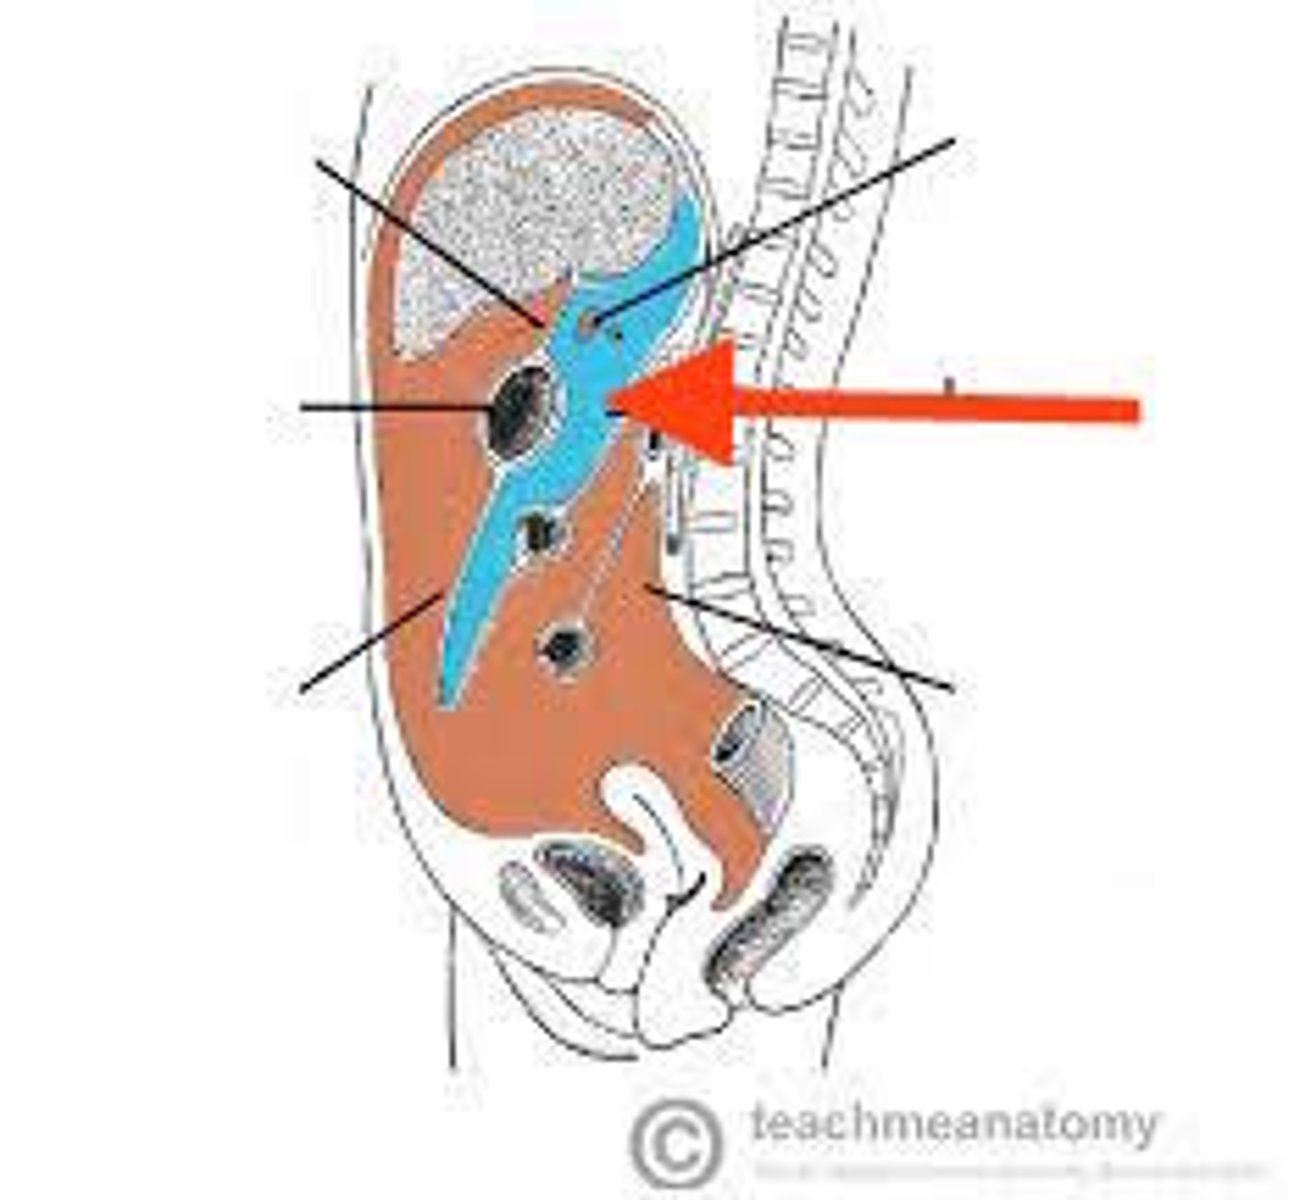

pararenal fat

perirenal fat

hilum (kidney)

left renal vein